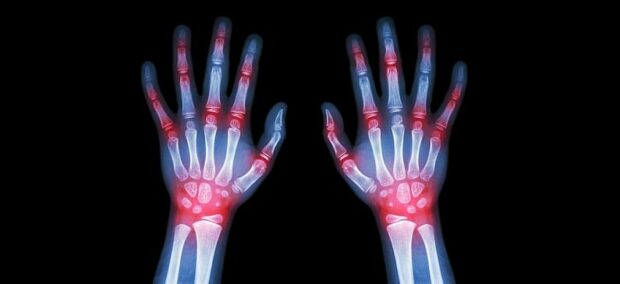

Η ρευματοειδής αρθρίτιδα είναι μια χρόνια και προοδευτικά επιδεινούμενη φλεγμονώδης πάθηση, η οποία πλήττει τις αρθρώσεις του σώματος, προκαλώντας ένα επώδυνο πρήξιμο και, στην πορεία, τη φθορά και την παραμόρφωση των αρθρώσεων. Το 1% έως 2% του πληθυσμού πάσχει από την πάθηση, η οποία επηρεάζει σημαντικά την ποιότητα ζωής των ασθενών.